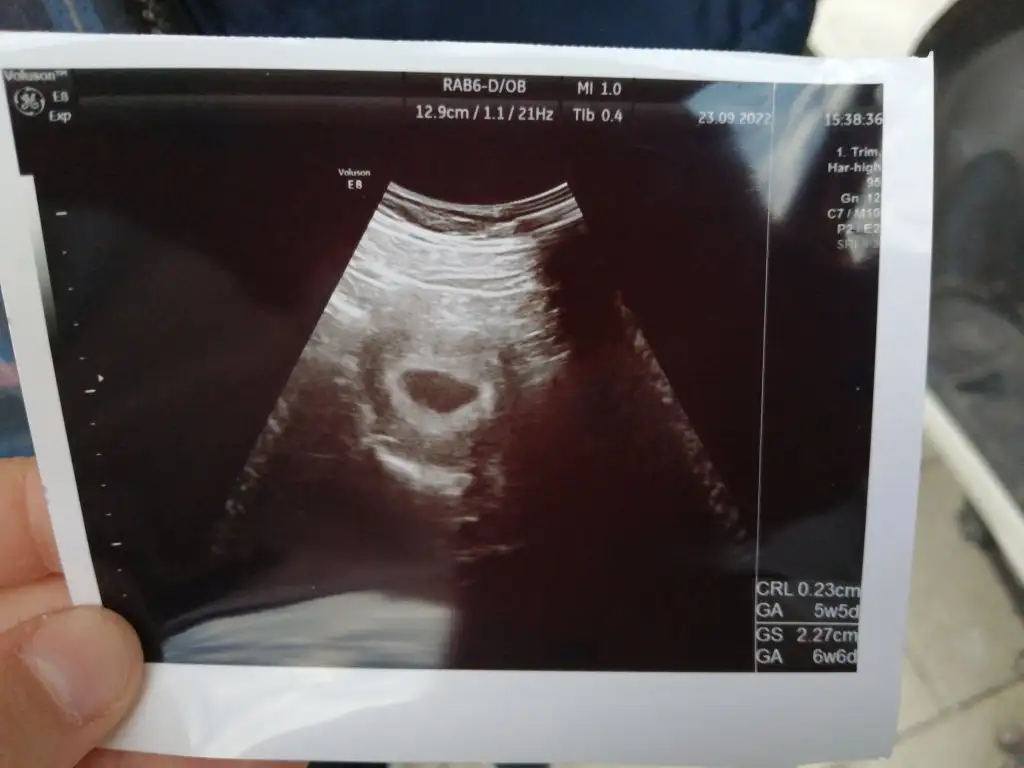

Kızlar bu gün keseyi görmeye gittim ama kendi doktorum İstanbul da oldugu başka bir özel hastane ye kadın doğuma gittim keseyi gördü ama bebeği çarşamba gel göre biliriz dedi şimdi gözükmez çok endişelendim yarın İstanbula kendi doktoruma gidicem acaba kalp atışlarını duya bilirmiyim? 6hafta oldu

Her şey normalmi diye sordum normal dedi Tüp bebek tedavisi gördüğüm hastanenin hemşiresine de atdım gözünüz aydın kese gözükmüş dedi

IMG-20220923-WA0010.webp